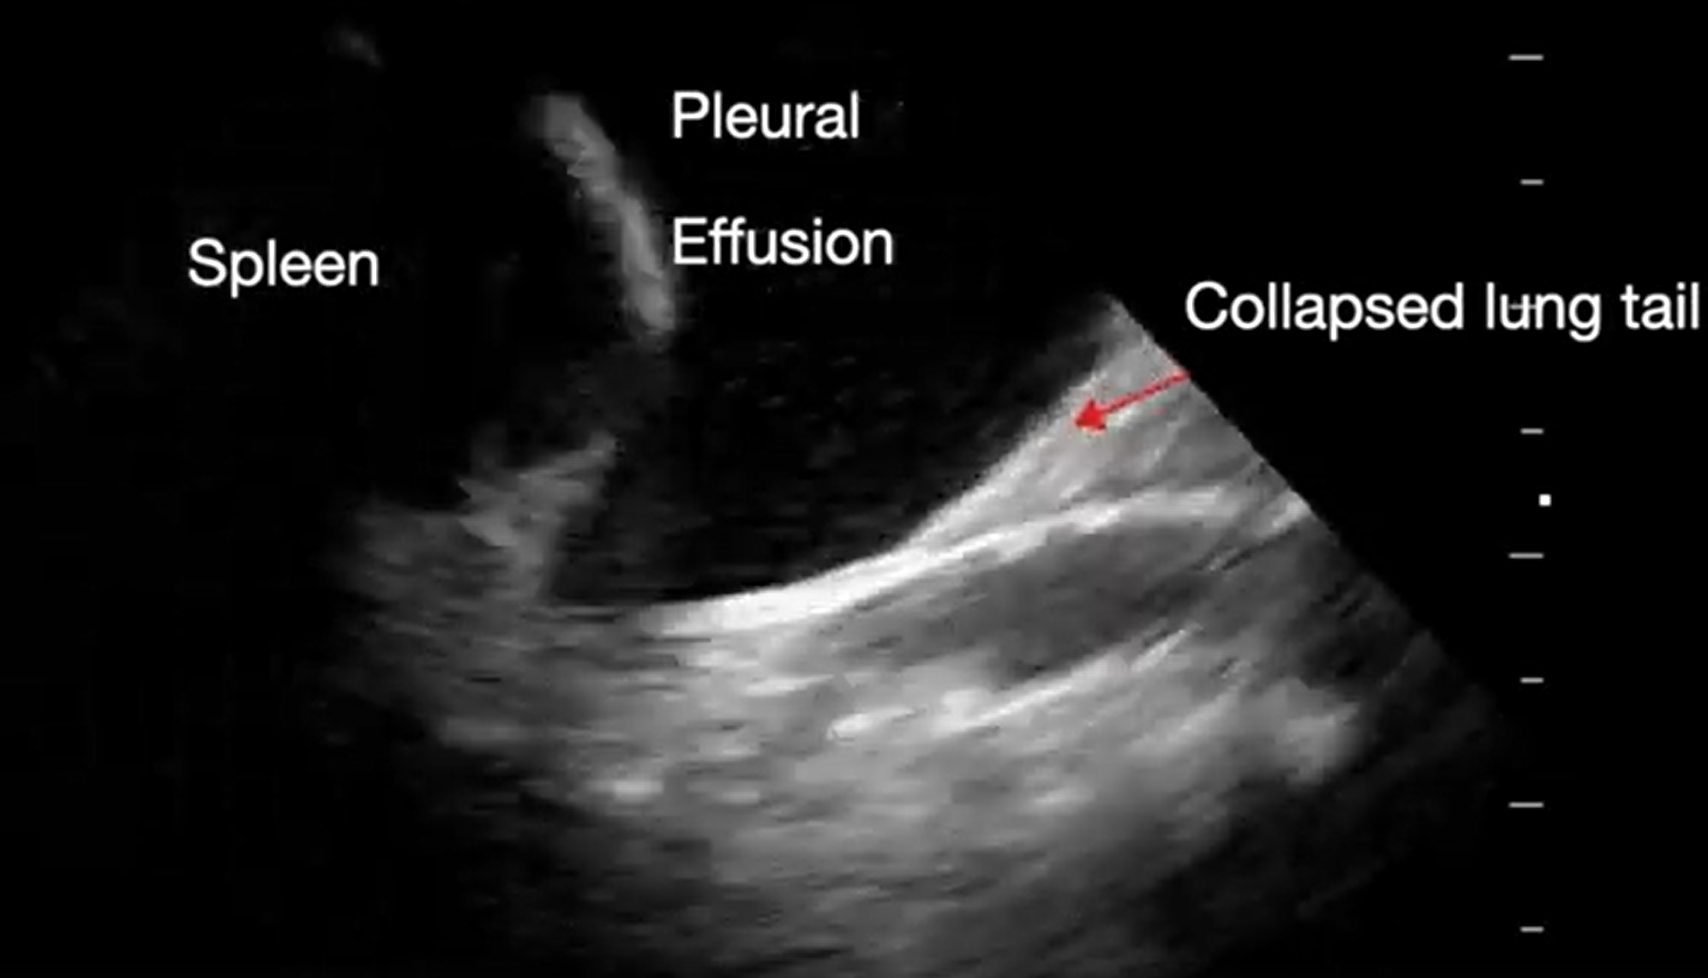

Pericardial tamponade is identified in 5%-22% of patient with PEA arrest.6,7 POCUS findings of pericardial tamponade include the presence of either small (acutely developing) or large (chronically developing) pericardial effusion, right atrial (RA) systolic collapse, right ventricular (RV) diastolic collapse, and plethoric inferior vena cava (IVC) (Videos 2 and 3). The diagnosis of tamponade using POCUS may be difficult in post-cardiac surgery patients who frequently present with a localized collection; transesophageal echocardiography (TEE) should then be used to make the diagnosis. A concomitant pleural effusion might potentially worsen the tamponade physiology. Therefore, imaging of the pleural space can be performed during chest compressions, with thoracentesis possibly reversing the tamponade physiology8 (Video 4).

Supplemental Video 4. Sonogram of the lateral inferior thorax demonstrating pleural effusion (click to view)